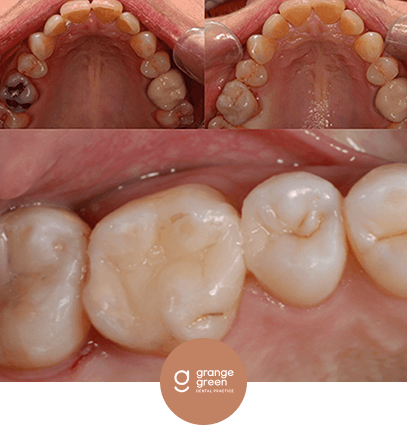

Here are just a few before and after cases to give you an idea of how we help to transform your smile and your confidence using treatments like orthodontics, bridges, veneers and composite fillings…